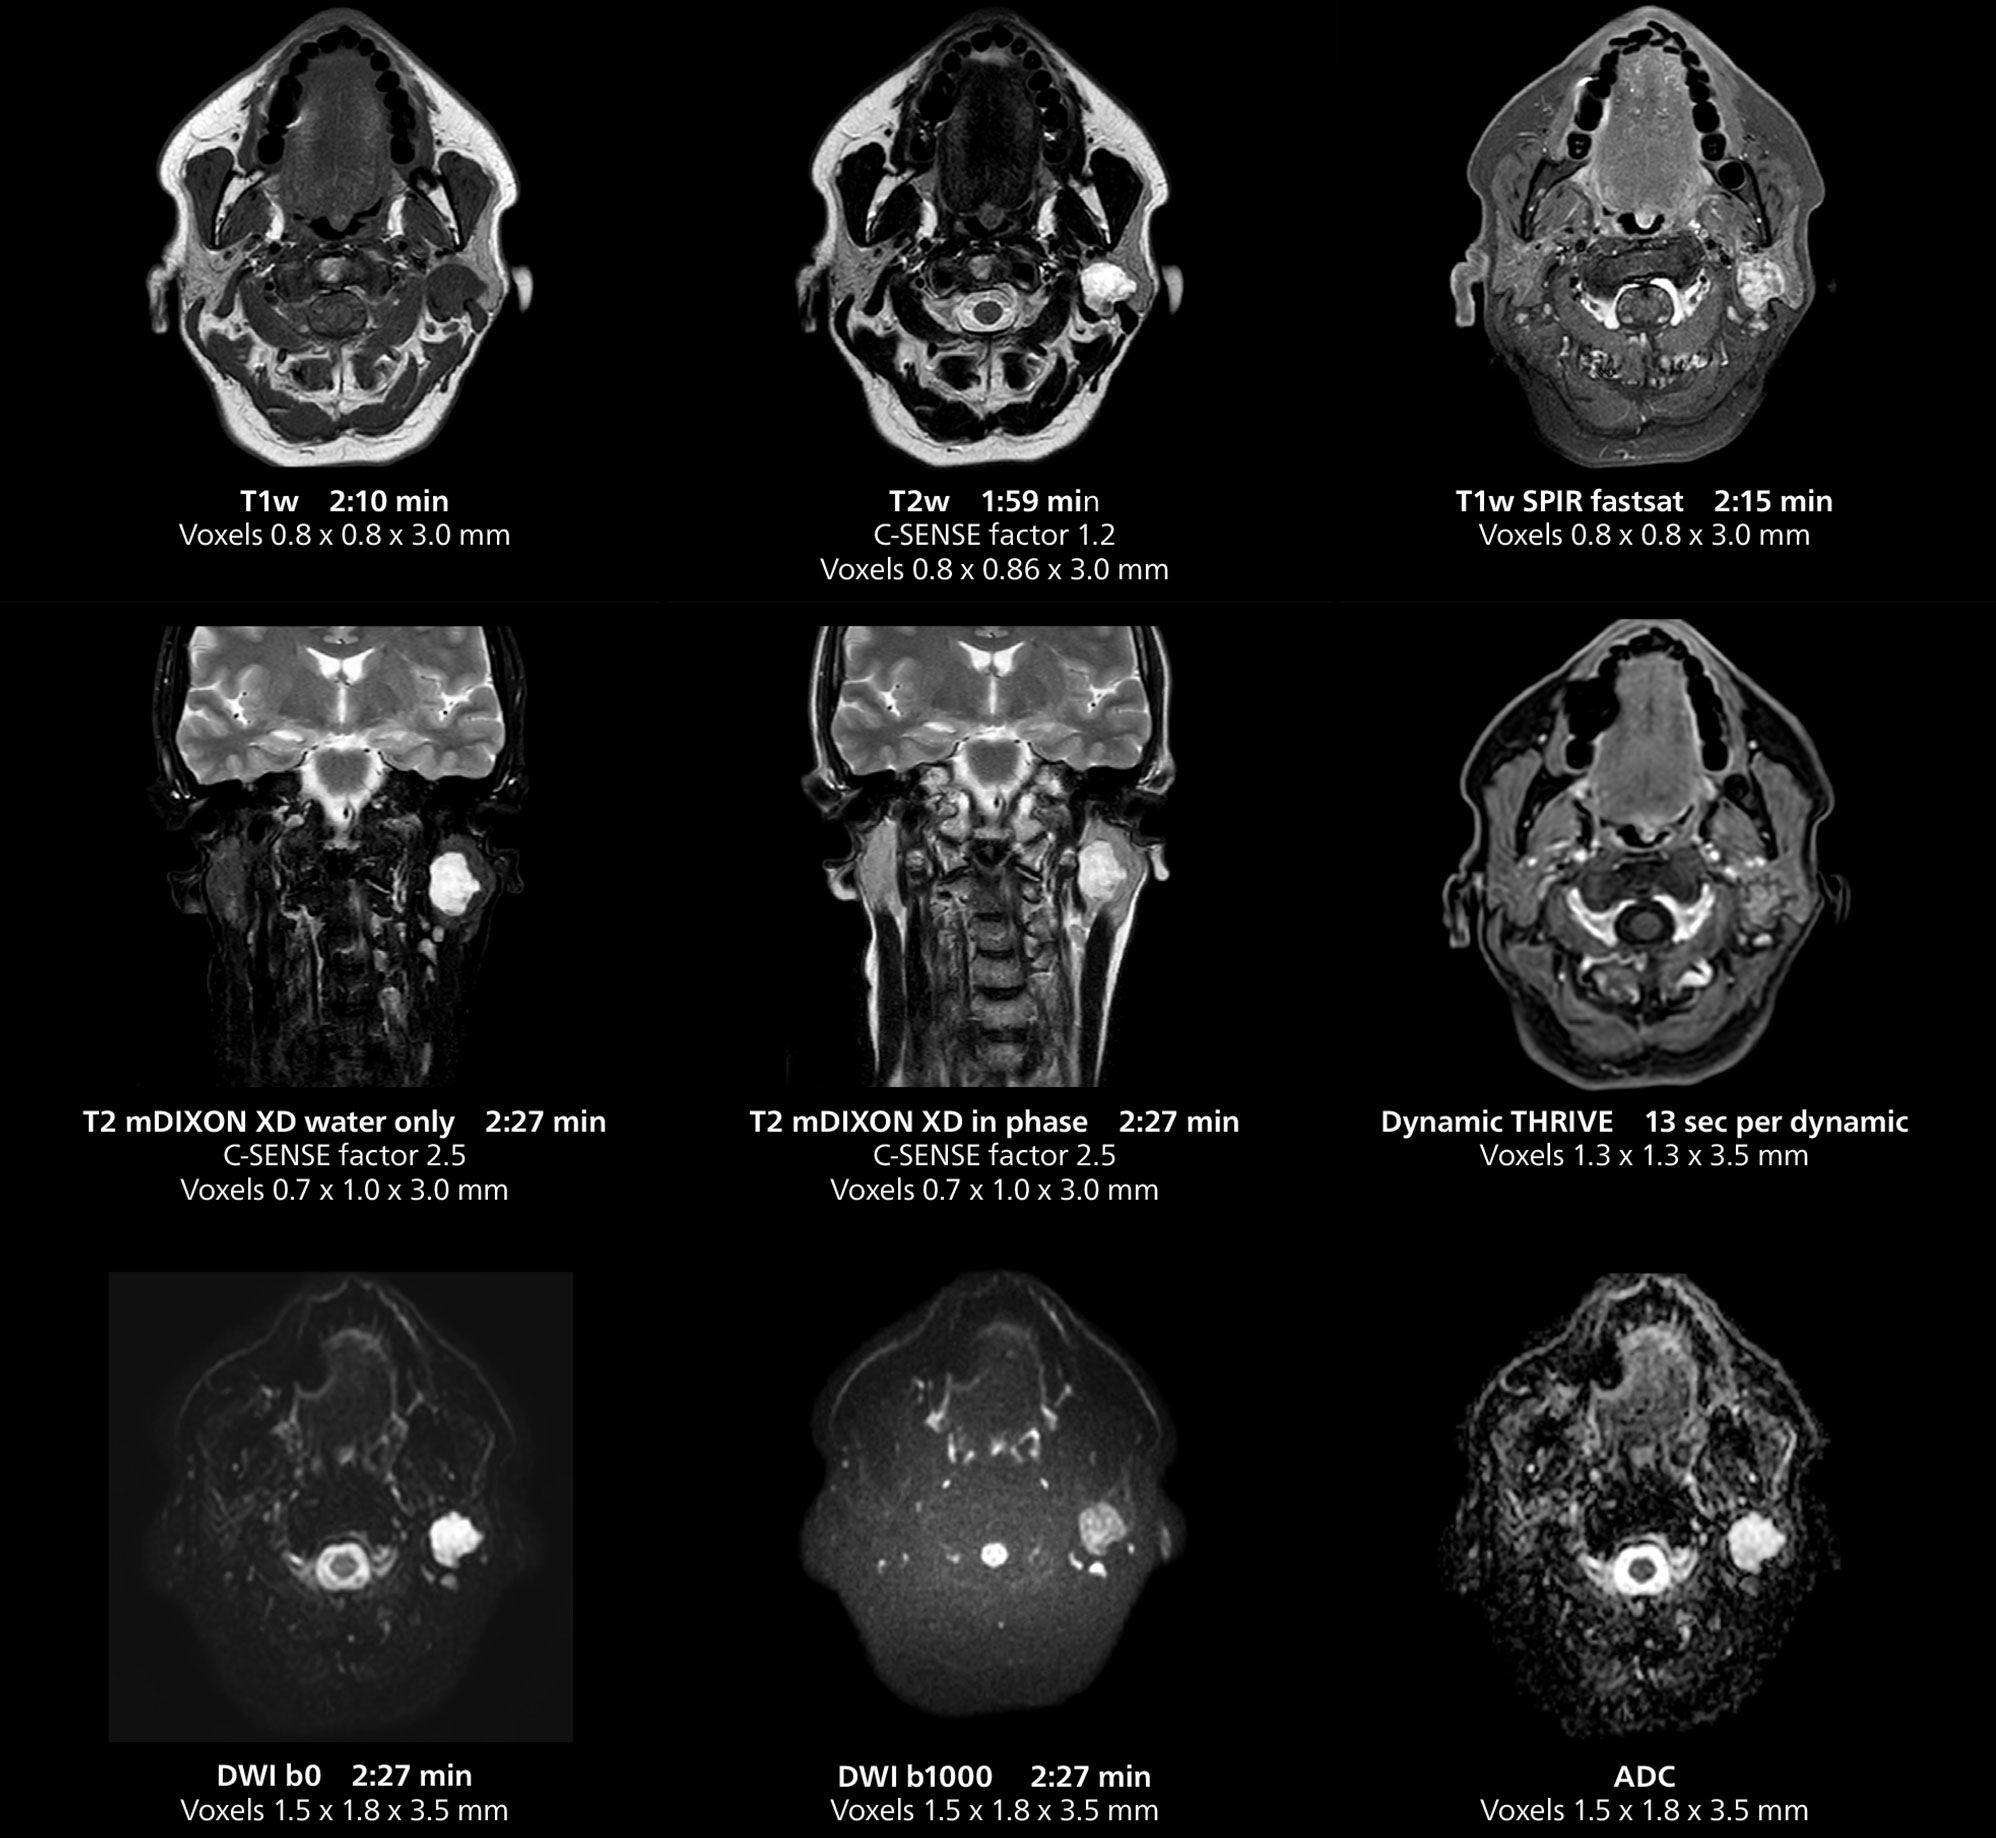

The MR 5300 with Compressed SENSE is up to 50%** faster for many exams. It can provide routine exams in less than 5 minutes and whole-body exams in less than 20 minutes. Saint-Augustin has taken advantage of that speed to create highly efficient protocols. The hospital’s standard stroke protocol is just about 8 minutes, and standard ENT, prostate PIRADS staging, and endometriosis studies all clock in at just about 10 minutes.***

“We have more speed in 3D sequences,” Dr. Gellée states. “With Compressed SENSE, we can replace two or three 2D scans withone high-quality 3D scan. High quality additional orientations are then obtained by post-processing of the 3D data set, thus saving scanning time.”

This MRI case illustrates imaging of salivary gland abnormalities with different sequences. Compressed SENSE allows to accelerate scanning while maintaining high quality. With mDIXON XD, different contrast types can be obtained from scanning one sequence.